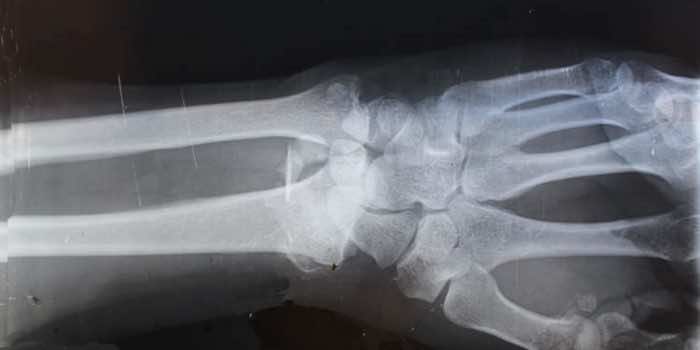

1994年,一名男子遭遇了一场严重的车祸,本应至少导致几处骨折。奇迹般地,他没有骨折,因为他拥有有史以来最致密、最强壮的骨头。

在x光片中,这些骨头没有骨折,令人惊讶的是,准确地说,这些骨头的密度似乎是正常骨头的八倍。他们把这名男子介绍给耶鲁大学骨骼中心主任卡尔·因索尼亚(Karl Insogna)。Insogna进行了额外的测试,但没有发现这种骨头的原因或副作用。后来,研究人员发现了几个骨骼密度相似的人,结果发现他们是那个人的远亲!